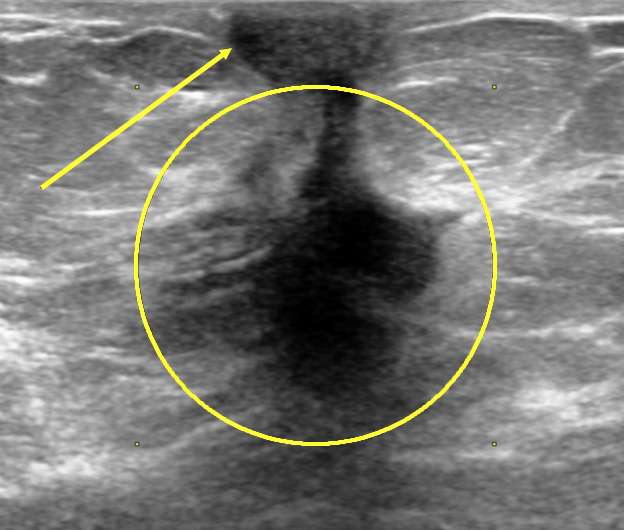

- Ultrasound: May further reveal distortion in the skin layers but is most helpful in further evaluating the presence of an underlying mass causing the retraction.

- Ultrasound: Provides a clear visualization of the thickness of the skin which can be easily measured and may be useful for evaluating for an underlying mass.